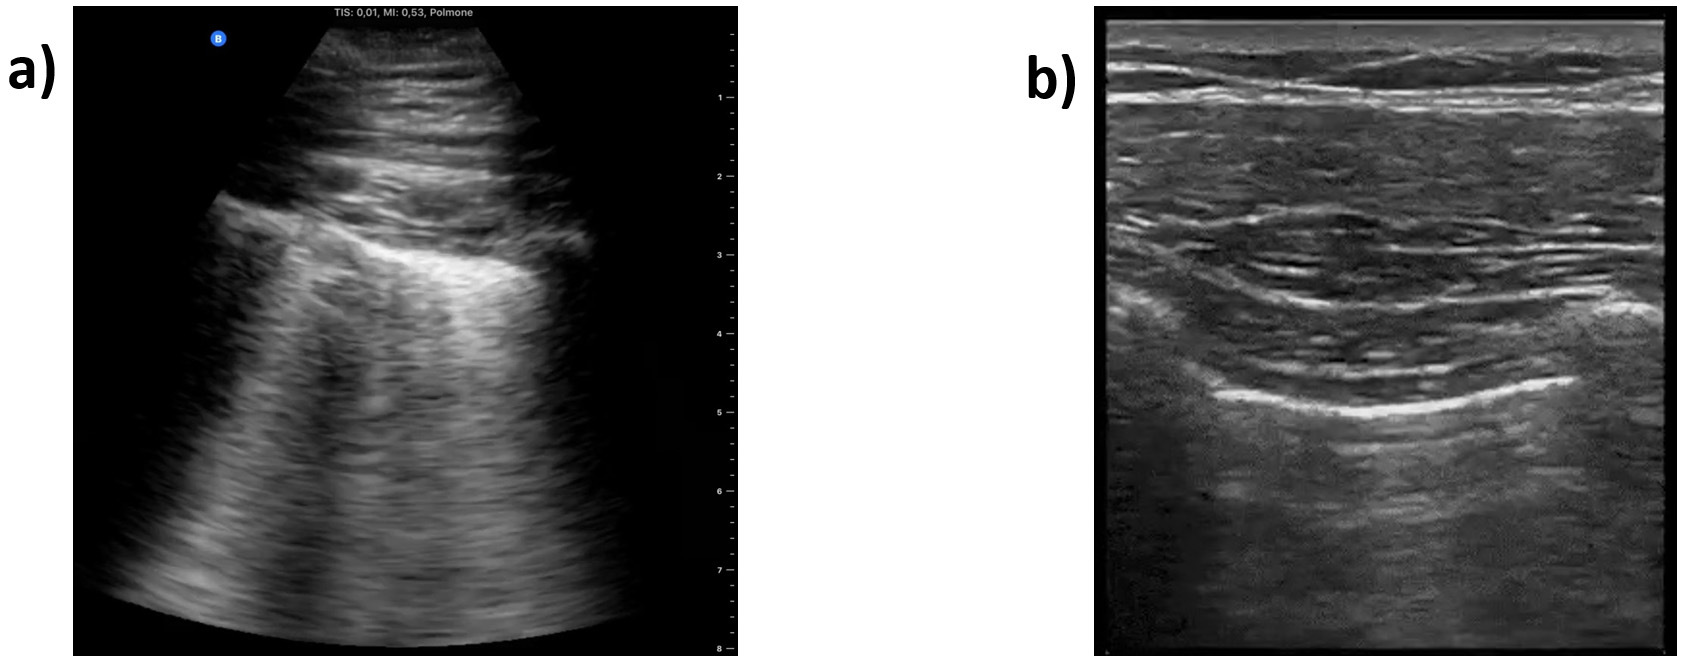

In order to validate the quality of images in the COVIDx-US dataset and ensure the existence of markers in the processed ultrasound images, our contributing clinician (S.K.) reviewed a randomly selected set of images and reported his findings and observations. Our contributing clinician (S.K.) is a practicing Internal Medicine and ICU specialist, certified in both specialties by the Royal College of Physicians of Canada. Fig. 9 shows three select images of COVID-19 positive cases, as examples, that were reviewed. The summary of our expert clinician’s report is as follows.

Fig. 9.Sample processed ultrasound images, reviewed and reported on by our contributing clinician. (a), (b) and (c) are all confirmed COVID-19 positive cases.

Case 1 (Fig. 9a). Our contributing clinician observed multiple pleural irregularities, including pleural thickening and the presence of sub-pleural consolidations which have been previously described as markers of COVID-19 disease severity [44]. These findings, together with the observed B-line profile, are indicative of a moderate to severe pulmonary disease.

Case 2 (Fig. 9b). This is an image of lung pleura in short depth. Our clinical expert observed abnormalities and irregularities in the pleura as it is thickened and “shredded” with hypoechoic signals suggesting consolidations and air bronchograms. Although a deeper view to assess for B-lines would be more optimal, these findings together suggest moderate airspace disease, most commonly on the basis of pneumonia.

Case 3 (Fig. 9c). This appears to be an image of lung pleura at depth

of ~5

Our expert clinician findings and observations confirmed the existence of identifiers and indicators of disease in the COVIDx-US dataset. AI-powered analytics solutions can exploit such indicators and patterns to monitor and classify COVID-19 cases. Based on our contributing clinician’s evolving experience, LUS has significant utility in the management of COVID-19 patients with respiratory symptoms. As a safe, rapid, reproducible, low-cost, and highly informative tool for assessing the severity of lung involvement, early studies suggest that it can be used to inform triage and treatment decisions [45]. To this end, several published LUS-based protocols are now undergoing validation in prospective clinical trials [46, 47]. Furthermore, several groups are now evaluating the potential utility of LUS in other settings, including the ICU where it could be used to track disease progression, and to evaluate patient candidacy and clinical response to various interventions including ventilator weaning, prone positioning, and lung recruitment maneuvers in patients with acute respiratory distress syndrome (ARDS) [40].